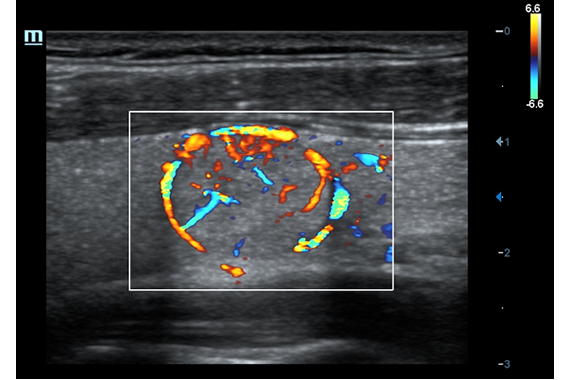

• HR Flow - режим отображения кровотока с высоким временным и пространственным разрешением для точной и однородной визуализации сосудов, в том числе самых мелких.

Цветовой допплер:

Да

HR Flow: